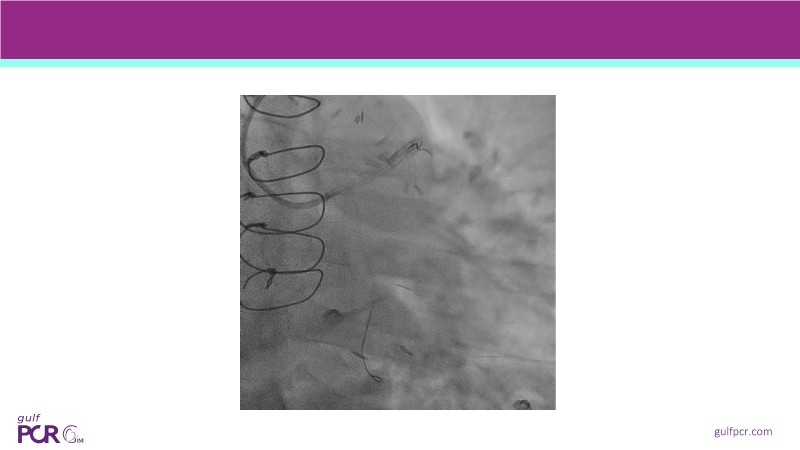

Calcified coronary lesions are a major challenge in PCI. This PCRGulf-GIM 2025 session showcases a complex case with intravascular imaging, highlighting how IVUS 123 guides each step.

From planning the procedure and understanding calcium distribution, to lesion preparation with modern modification tools, and post-PCI assessment to confirm stent expansion and detect complications, this session demonstrates practical, imaging-driven strategies.

Learn how careful preparation and modern techniques improve outcomes in treating severe calcium, calcified nodules, and in-stent restenosis.